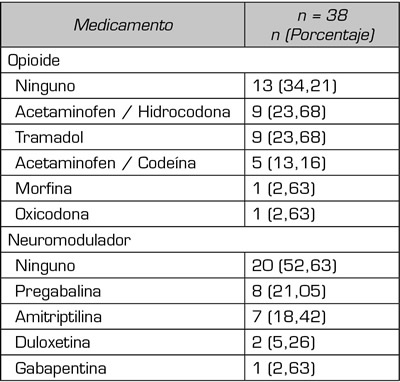

Dentro del manejo farmacológico, se evidenció la disminución del consumo diario de analgésicos posterior al bloqueo de nervios cluneales en el 65 % de los pacientes. El acetaminofén representó el 88,5 % (n = 34) de los fármacos prescritos, el 65,7 % (n = 25) recibió opioides, hidrocodona el 23 % y tramadol el 23 %; los neuromoduladores más prescritos fueron pregabalina 21 % y amitriptilina 18 %; y AINE 11,4 % (Tabla III).

Tabla III. Uso de opioides y neuromoduladores antes del bloqueo cluneal.